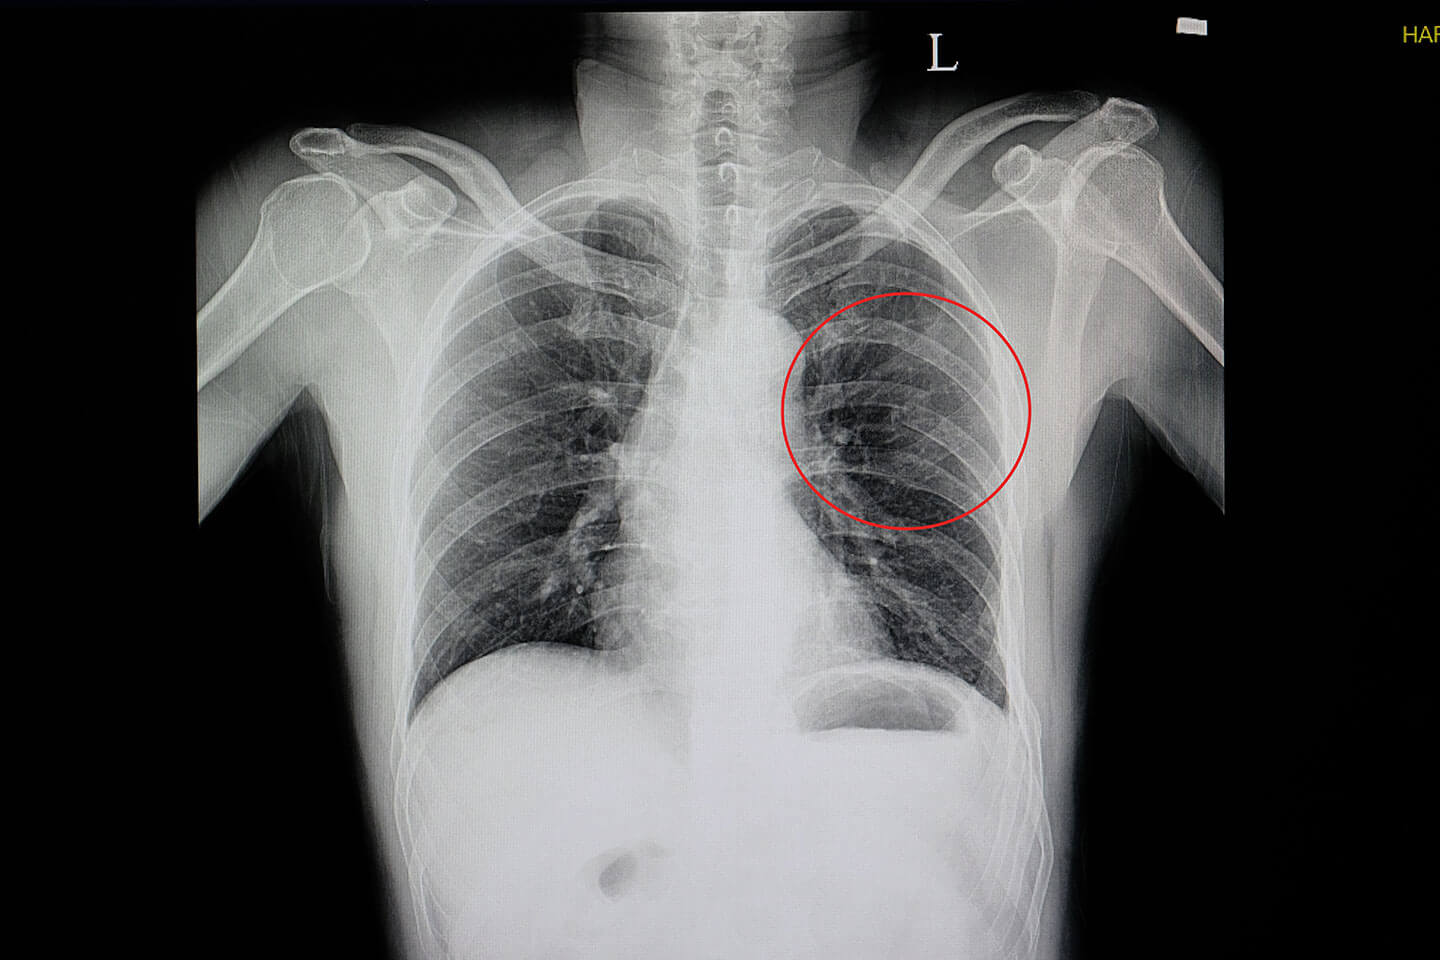

A broken rib typically causes sharp pain. To diagnose a rib injury, it’s best to see a medical professional who can look at your injuries with professional tools and technology. You may also feel or hear a crack or pop when the.

Take slow, deep breaths and cough regularly to expand your lungs, use an incentive spirometer if asked to do so, get up and move around when you’re not sleeping,. When visiting your doctor, they will most likely be able to diagnose your injury simply by pushing on your chest and doing a physical exam. The pain you feel with a broken rib typically occurs or even worsens when you: